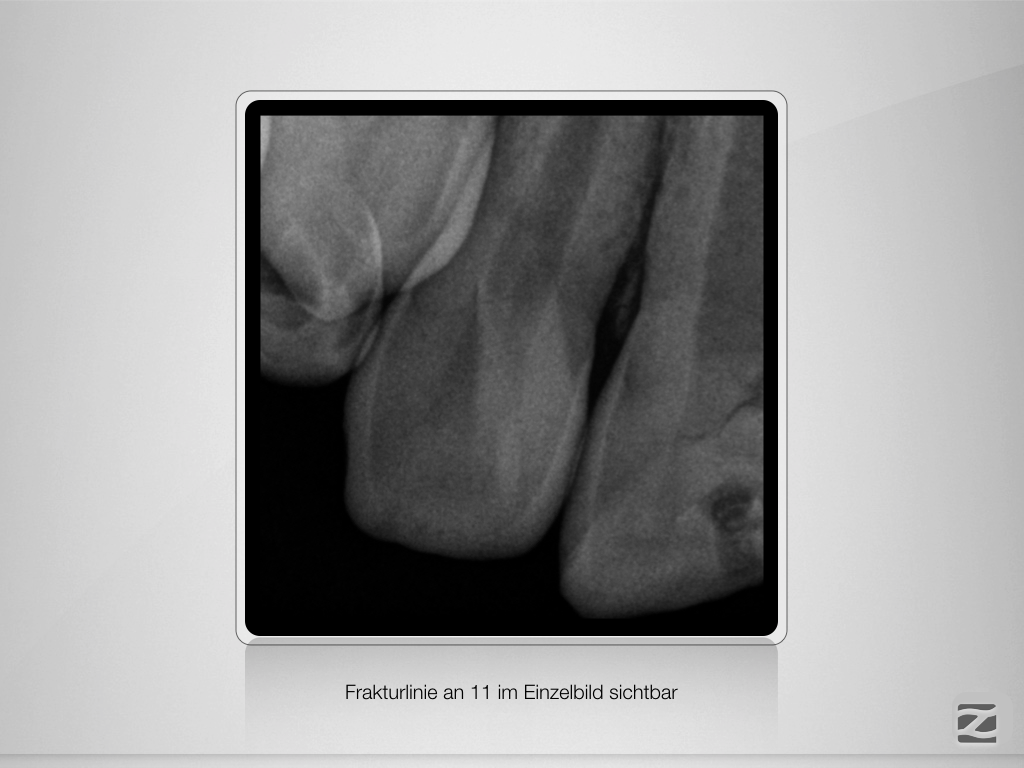

Frontzahntrauma – das klinische Vorgehen.